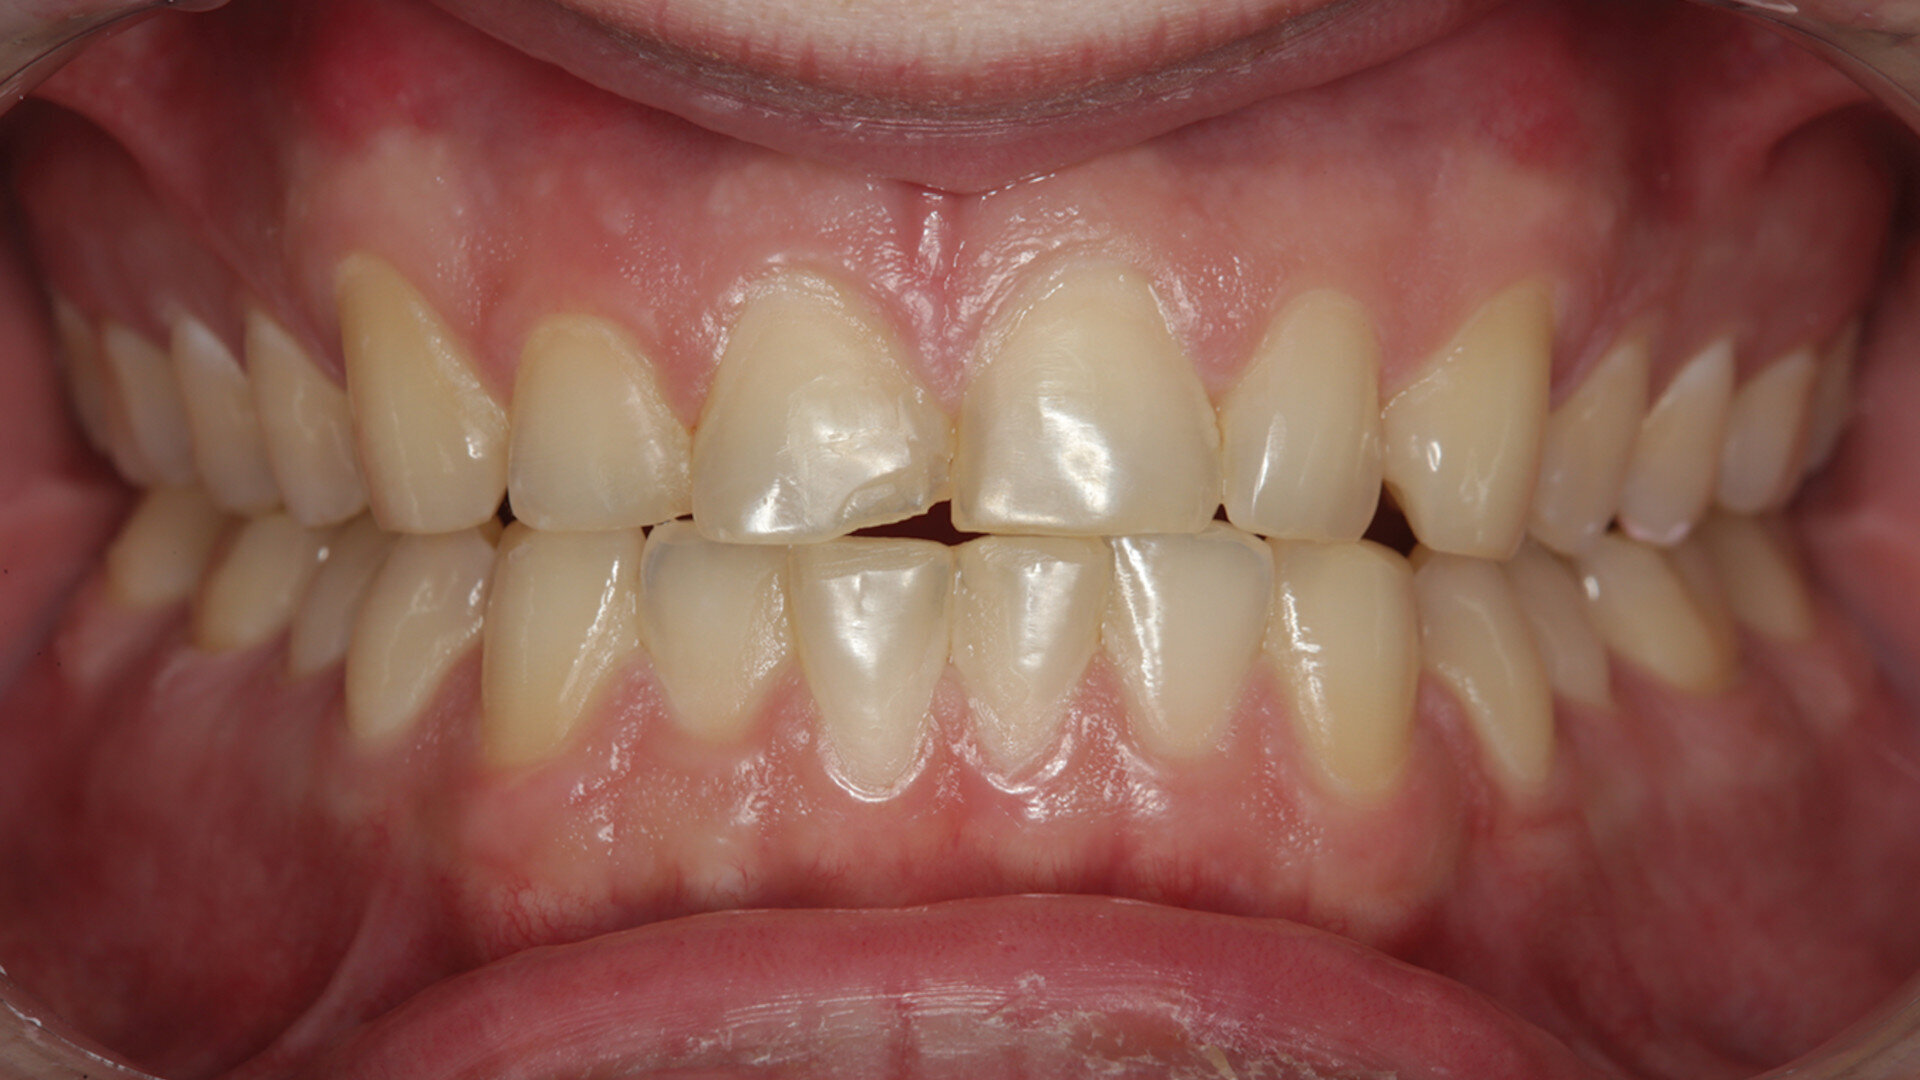

Fig. 1: Pre-op retracted facial view of the fractured composite restoration on tooth #11 with the teeth in maximum intercuspation. (All images: Robert A. Lowe)

The patient presented with a fractured Class IV mesial–incisal composite restoration on tooth #11 (Fig. 1). It had been repaired three times dur­ing the past year and had fractured again. Was this due to poor technique, maybe inferior materials? More than likely, it was due to occlusion. Aside from the amount of composite on the facial sur­face that extended beyond the fractured area, most of the palatal surface of the tooth was worn through to the dentine due to hyperfunction in protrusive and lateral excursion over many years, creating a functional and aes­thetic dilemma for the patient. A “conservative” approach may have been to bond the tooth again with composite and hope for the best. However, this may not have been the best long-term approach considering the functional stress in this area, even with the best tooth alignment. After all, how conservative is it to continually assault the tooth with rotary instrumentation to keep fixing a composite that continues to fracture?